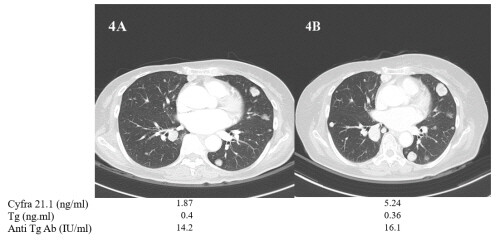

| ▲폐전이가 있는 57세 갑상선암 환자의 폐 CT 1년 전후 사진, 사진을 보면 암이 커지고 전이가 진행하는것을 볼수 있다. Cyfra 21.1 (ng/ml) 수치는 1.87에서 5.24로 증가하는 추세로 갑상선암이 진행되는 것을 알 수 있다. 하지만 현재 지표로 쓰이는 티로글로불린(ng/ml)은 같은 기간 동안 0.4에서 0.36으로 변화가 없어 병의 진행을 알 수가 없다. (사진=의정부성모병원 제공) |